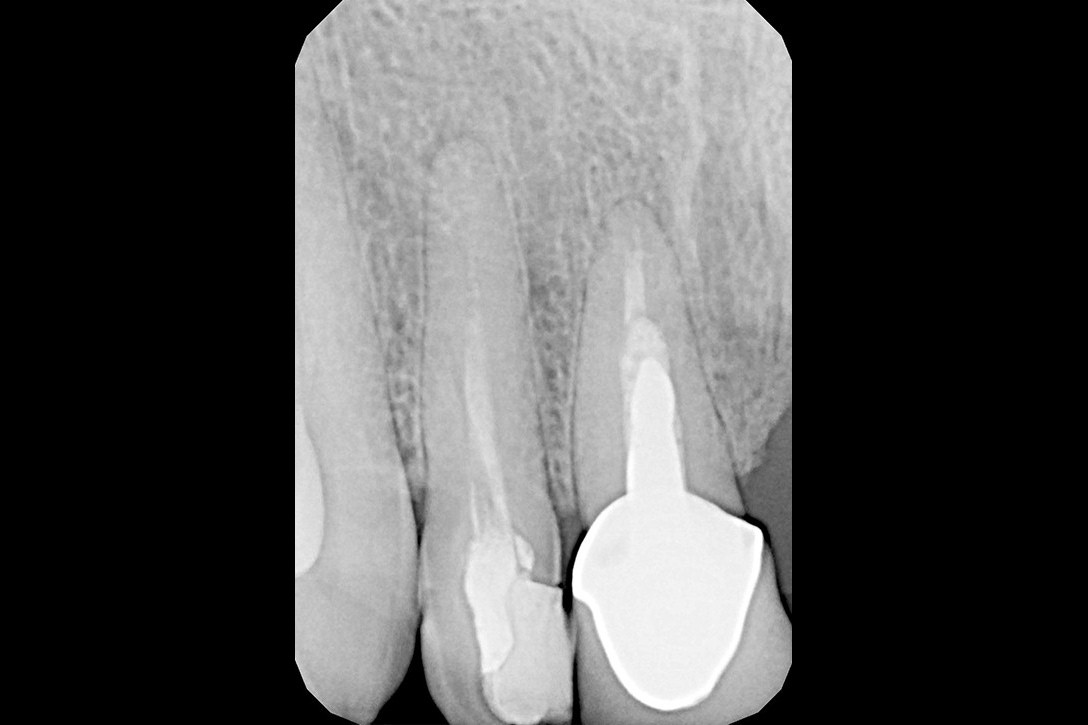

W przypadku zaawansowanych postaci zapaleń miazgi oraz zapalenia tkanek okołowierzchołkowych obraz radiologiczny jest warunkiem rozpoznania. W takiej sytuacji standardem diagnostycznym są zdjęcia przylegające zęba, często wykonywane przy użyciu radiowizjografii na fotelu stomatologicznym w trakcie leczenia zęba. Przydatne jest również badanie RTG OPG pantomograficzne, które pokazuje w dwuwymiarowym obrazie zarówno uzębienie, jak i cały układ kostny szczęki oraz żuchwy.

Stożkowa tomografia komputerowa CBCT, ze względu na dokładne, trójwymiarowe obrazowanie 3D, bez zniekształceń ukazuje szczegóły anatomii zęba oraz okolicznych tkanek, wyjaśniając nierzadko problemy niemożliwe do zdiagnozowania standardowymi metodami.

Zarówno ziarniniak okołowierzchołkowy, jak i torbiel zębopochodna uszkadzają struktury okolicznej tkanki kostnej. Podobny proces jeszcze do niedawna był książkowym wskazaniem do interwencji chirurgicznej (resekcja wierzchołka korzenia, hemisekcja korzenia zęba wielokorzeniowego) lub nawet usunięcia zęba.

By uniknąć niedokładności leczenia, oprócz sumiennego wykonania procedur należy diagnostycznie kontrolować każdy etap leczniczy przy użyciu rtg. Szansą dla niedokładnie wypełnionego kanałowo zęba jest jego powtórne leczenie endodontyczne, zwane REENDO.

Konieczność powtórnego leczenia endodontycznego może zaistnieć w sytuacji, gdy kanały zęba nie zostały wypełnione do ich anatomicznego wierzchołka lub w trakcie leczenia doszło do złamania i pozostawienia ułamanego narzędzia w świetle kanału korzeniowego. O konieczności powtórnego leczenia endodontycznego może również zadecydować zmiana zapalna przy wierzchołku korzenia, która jest widoczna jedynie na obrazie kontrolnego zdjęcia rtg.

Prawidłowo wyleczony endodontycznie ząb z powodzeniem może służyć przez wiele lat życia pacjenta. Poprawa jego funkcji możliwa jest dzięki skutecznej odbudowie protetycznej, poprzez wzmocnienie go wkładami koronowo-korzeniowymi z włókna szklanego i wykonanie korony protetycznej.